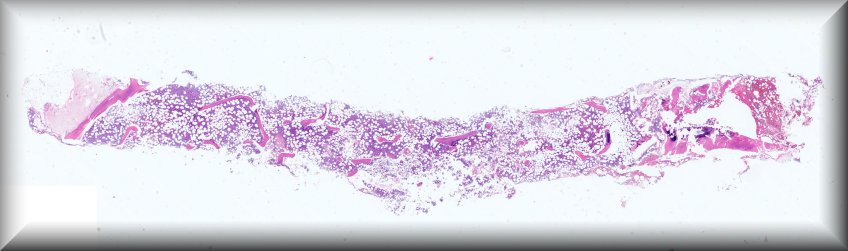

Caso 2.- Roger Eduardo Casco Zuniga; Evelyn Beatriz Troncoso Hernández; Svetlana Shalygina; Paola Andrea Chilito Paredes; José Luis Losa García.

Hospital General Universitario de Alicante.

Varón de 79 años, con antecedente de mieloma múltiple en actual tratamiento. Acude a servicio de urgencias por astenia de 4 días de evolución y presencia de pancitopenias persistente a pesar de tratamiento. Se realiza biopsia de médula ósea en el que se observa infiltración difusa por células pequeñas de estirpe linfoide y un 15% aproximado de células plasmáticas con restricción de cadenas ligeras Kappa.